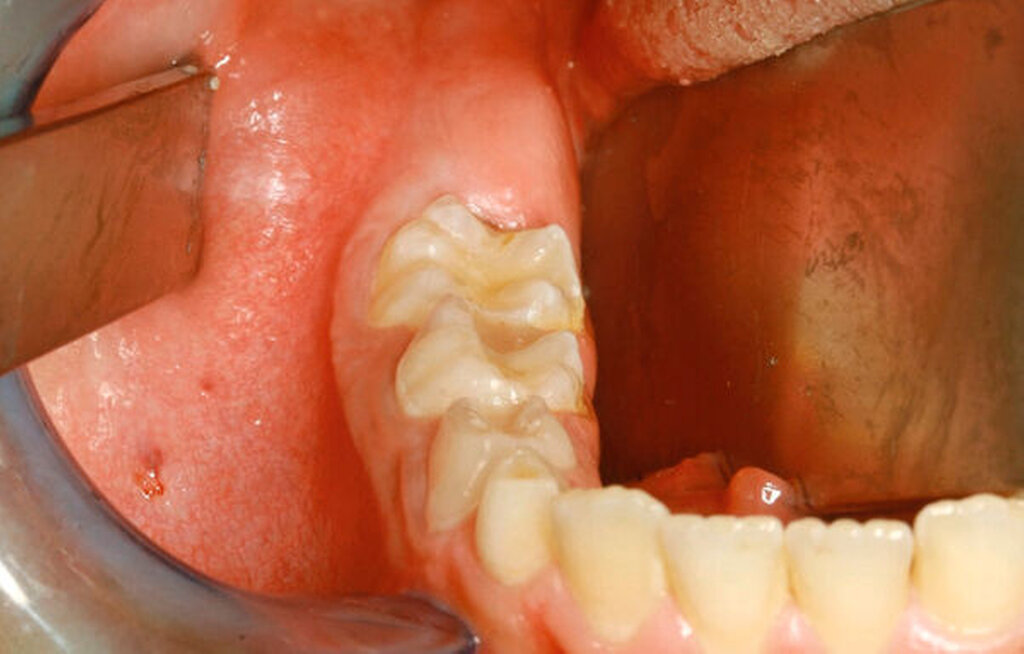

Anamnestisch berichtete der Junge von keinerlei Einschränkungen, Schmerzen oder sonstigen Auffälligkeiten. Im Rahmen der klinischen Untersuchung zeigten sich zudem keine Auffälligkeiten im Bereich des N. alveolaris inferior / N. mentalis rechts. Intraoral war die Schleimhaut im Bereich des Kieferwinkels intakt, ohne Anhalt für eine entzündliche Veränderung. Palpatorisch stellte sich eine dezente, schmerzlose knöcherne Auftreibung vestibulär dar. Zur weiteren Diagnostik und OP-Planung wurde eine digitale Volumentomografie angefertigt.

Unter der Vollnarkose erfolgte zunächst eine gründliche intraorale Inspektion, wobei sich im Bereich des Kieferwinkels rechts die knöcherne Ausbuchtung nach vestibulär deutlich darstellte (Abbildung 2). Es folgten eine Infiltrationsanästhesie im Bereich des rechten Kieferwinkels und anschließend eine marginale Inzision regio 85–46 mit Fortführung nach distal-vestibulär sowie anteriorer Entlastung. Nach Bildung eines Mukoperiostlappens wurde die Raumforderung in regio 47 mittels Osteotomie unter Schutz des N. lingualis dargestellt.